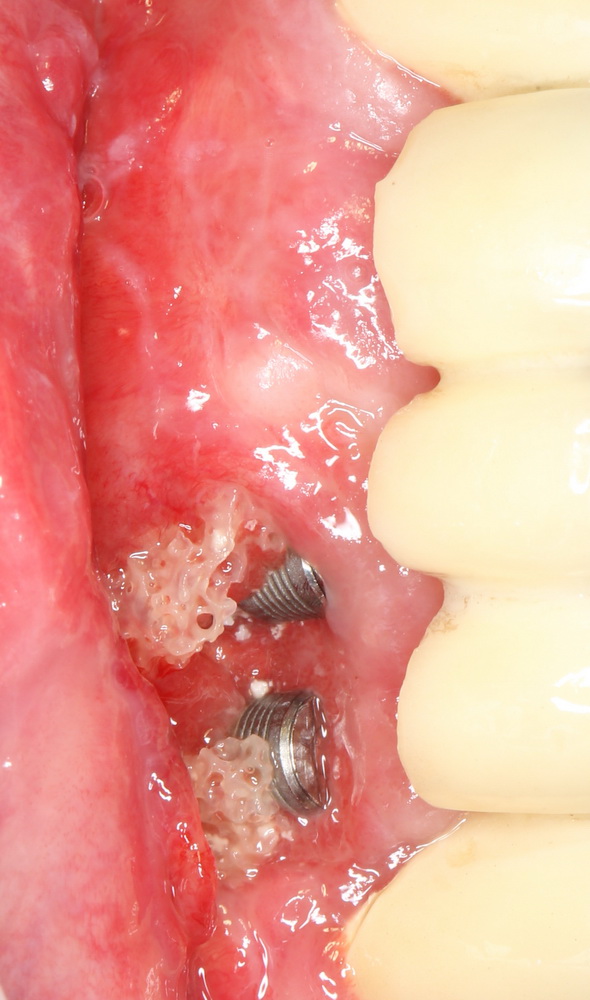

Уж не знаю, с чем это связано, но врачи пугают пациентов именно исчезновением имплантатов или компонентов для их протезирования. Да, действительно, абсолютное большинство используемых в России имплантационных систем имеют иностранное происхождение, следовательно с их поставками могут быть серьёзные проблемы.

Не остались в стороне барыги (самые нехорошие люди на свете), местами скупившие весь склад имплантатов в расчете на перепродажу подороже — из-за чего некоторые поставщики были вынуждены ввести отпускные правила на имплантаты, типа «не более 5 штук в одни руки в день».

В итоге, стоимость имплантации в некоторых клиниках существенно выросла, а сами клиники требуют от пациентов авансов за предстоящее лечение, меняют согласованные ранее планы, просят доплатить и т. д.

Имплантаты и имплантационные системы — это то, что импортозамещается проще всего.

Во-первых, судя по реестру регистрационных удостоверений Росздравнадзора, сегодня в Российской Федерации зарегистрировано примерно 140 (!!!) различных имплантационных систем. Из них больше 70 (!!!) находятся в обороте — их покупают клиники, их ставят пациентам. Для крупнейших производителей, вроде Dentsply Sirona Implants, HiOssen, Nobel Biocare, Straumann AG и т. д. наша страна является рынком №1 или, как минимум, в первой пятёрке рынков. Конкуренция среди имплантационных систем чрезвычайно высока, оригинальных продуктов нет — поэтому ни один вменяемый производитель имплантатов не уступит конкурентам свою долю рынка, на завоевание которой ушли годы и миллионы долларов.

Во-вторых, судя по тому же реестру Росздравнадзора, в нашей стране производят больше 20 собственных имплантационных систем. Ежу понятно, что на некоторые из них просто клеят наклейки «сделано в России», а часть российских производителей внаглую обманывают своих потребителей. Но даже то немногое, что производится честно и без обмана — вполне себе конкурентоспособный продукт, но, что самое главное — это свидетельство того, что у нас есть и технология, и сырье, и всё необходимое для того, чтобы развивать собственное производство имплантационных систем.

В-третьих, (кстати, о производстве) — развитие цифровых технологий и высокоточного фрезерования, с одной стороны, наводнило нашу страну контрафактом, «самодельными» аналогами, абатментами, титановыми основаниями и т. д., с другой — сделало нас совершенно независимыми от поставок этих самых компонентов из-за рубежа. Поэтому вам после установки имплантата совершенно не нужно беспокоиться о том, будут ли в наличии компоненты для его протезирования. Сейчас уверенно можно сказать, что компоненты будут.